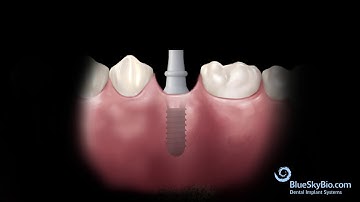

The return of tissue level implants